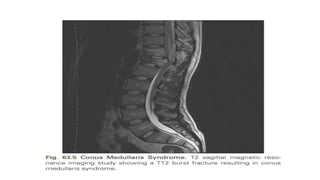

Conus Medullaris Syndrome

• There is high probability that injuries to the thoracolumbar region can

involve the conus medullaris.

• The conus medullaris represents the transition of the spinal cord from

the central nervous system to the peripheral nervous system.

• The location of this region is highly variable—between the T12 and L1

disk space to the middle third of L2 in the majority of the population.

• The lumbar parasympathetic fibers, sacral sympathetic fibers, and

sacral somatic nerves originate in the conus medullaris.

• The classic presentation entails lower-extremity weakness, absent

lower-limb reflexes, and saddle anesthesia.

• There is usually mixed UMN and LMN involvement.

• Loss of the bulbocavernosus and anal reflexes is permanent,

differentiating conus medullaris syndrome from SCIs that have a

return of these reflexes within 48 hours of the injury.

• Patients typically have an areflexic bowel and bladder (low-pressure,

high-capacity bladder).

• The most common injuries to the vertebral column resulting in this

condition are burst fractures or fracture-dislocation.

• There is no strong clinical evidence favoring surgical intervention over

nonsurgical intervention for conus medullaris injuries.

• Furthermore, if surgical intervention is performed, there is no

compelling evidence to suggest that earlier decompression affects

functional outcome.